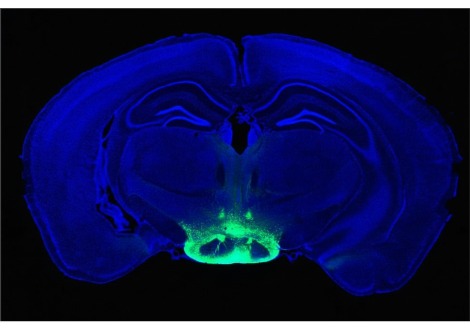

في الذباب والفئران ، تتسبب السيتوكينات المنبعثة من الأورام في الجسم في حدوث تقاطعات خلوية تحمي الدماغ بشكل طبيعي من الجزيئات المنتشرة من الانفتاح ، كما هو موضح هنا من خلال انتشار صبغة التتبع.

يتكون الحاجز الدموي الدماغي في الذباب من الخلايا الدبقية التي تحمي الدماغ من الدورة الدموية المفتوحة الدم اللامفوية ، وهو سائل الدورة الدموية في ذبابة الفاكهة. قام الباحثون بفحص ما إذا كان الحاجز الدموي الدماغي سليمًا عن طريق حقن صبغة في السائل الدم اللامفوي. ووجدوا أن الصبغة دخلت في أدمغة الذباب المصاب بالأورام ولكن ليس في أدمغة عناصر التحكم .